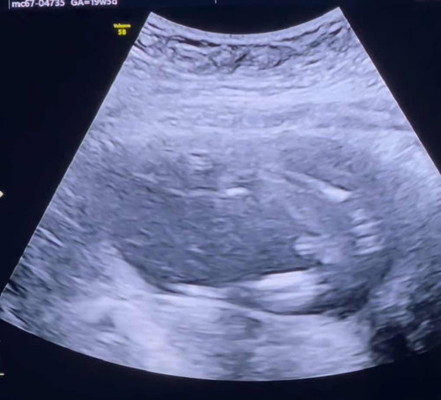

ทายเพศน้องกันค่ะแม่ๆ 😋

ทายเพศน้องกันจ้า ^^ ทีมมีนาคม 68 ตื่นเต้นมากๆฮะ

ไม่ต้องทายแล้วค้าาา จุ๊ดจู๋ลอยเด่นขนาดนี้ ของเราก็แบบนี้เลยค้า🤣